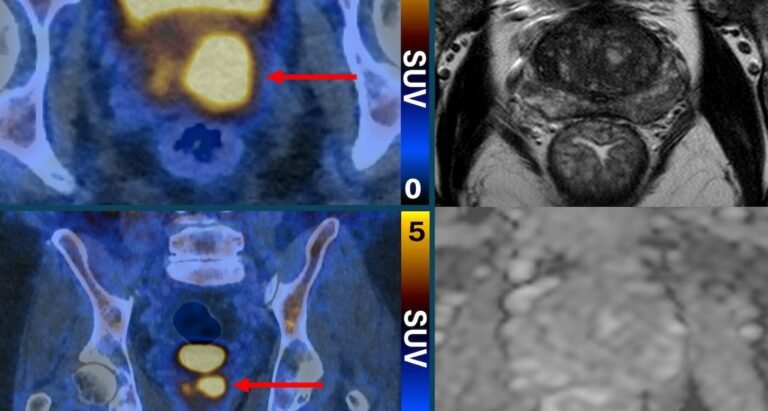

Clinically significant prostate cancer cells glow in PSMA PET/CT scan despite normal inconclusive MRI Scan SWNS

The state of the art imaging test uses a molecule that binds to prostate cancer cells, causing them to “light up in a remarkable way”—appearing as bright spots in the scanning image.

Their PSMA PET/CT scan identifies the more aggressive prostate cancer cells, which are potentially harmful and may need treatment—and could help reduce the risk of over-diagnosis by determining which cancers are low-risk and will never cause harm.

“PSMA PET/CT scanning makes prostate cancer cells light up in a remarkable way, particularly in more aggressive cancers,” said Dr. Buteau.